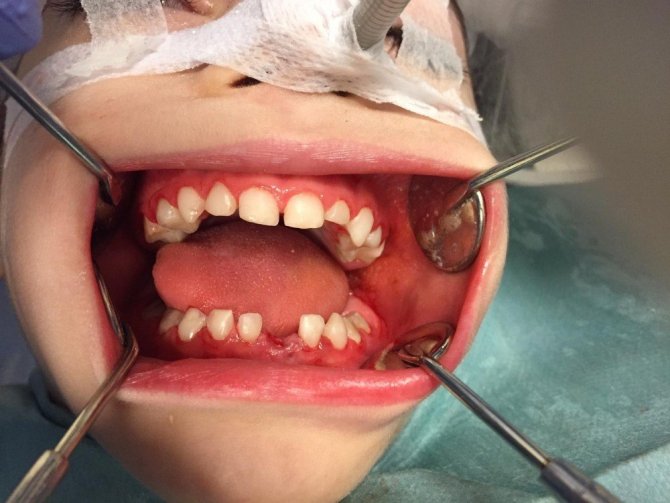

Koruyucu ve önleyici diş tedavilerinin de yapıldığı merkezde, ilçedeki çocukların yanı sıra bugüne kadar 940 engelli bireyin muayenesi gerçekleştirildi. 360 engelli bireyin diş tedavileri, genel anestezi altında yapıldı. 2016 Ekim ayından itibaren engelli hastaların genel anestezi altında tedavilerinin yapıldığı merkezde, 18 Nisan 2019 tarihinde ise zorlu bir operasyonla 5 yaşındaki engelli bir bireyin tüm dişlerine müdahale edildi. Engeli dolaysıyla akranları gibi dişlerini fırçalayamayan ve bakımını geçekleştiremeyen Spida Bifida ve Hidrosefali hastası çocuğun dişleri adeta yenilendi.

Operasyonda, önce çocuğun Periapikal röntgeni çekilerek dişlerinin mevcut durumu ortaya kondu. Ardından 5 yaşındaki engelli bireyin, 16 süt dişine kuafaj işlemi, 3 süt dişine kanal tedavisi yapıldı ve 1 süt dişinin çekimi gerçekleştirildi. Tedavi sırasında ayrıca tüm dişlere detertraj (diş taşı temizliği), polisaj ve yerel flour uygulaması yapıldı. Gerçekleştirilen tedavinin ardından, klinikte özel bir bölüme alınan engelli bireyin uyanması beklendi ve yapılan tetkiklerde sağlık durumunun iyi olduğu tespit edildi. Yeni dişlerine kavuşan ve dişlerini kaybetme tehlikesinden kurtulan engelli vatandaşın, bazı diş ağrılarından da kurtulduğu öğrenildi.